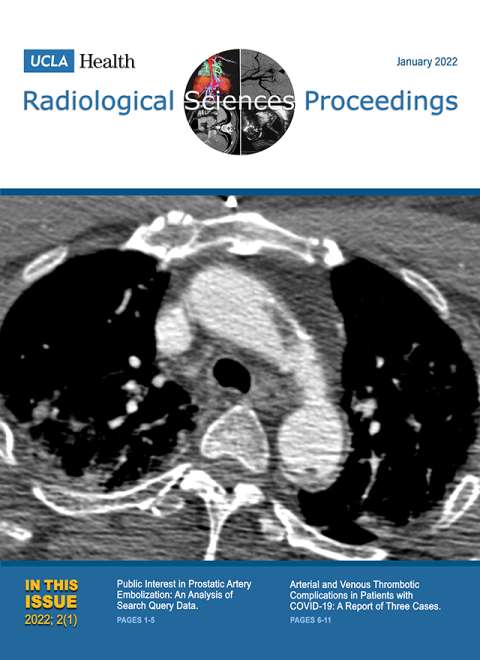

January 2021

Volume 1, Issue 1

- Giant Hepatic Regenerative Nodule in a 17-year-old with Alagille Syndrome

- Closed Sagittal Band Injury: A Case Report.

October 2021

Volume 1, Issue 4

- Electronic Integrated Diagnostic Report for Presenting Results of Breast Imaging and Breast Biopsy

- Iatrogenic Axillary Pseudoaneurysm Caused by Ultrasound-guided, Vacuum-assisted Biopsy of the Axillary Lymph Node: A Case Report

- Emergency Intravascular Aortic and Iliac Artery Lithotripsy to Facilitate Thoracic Endovascular Aortic Repair of a Ruptured Thoracic Aortic Aneurysm: A Case Report

- Acute Large Bowel Obstruction due to Pelvic Endometriosis: A Case Report